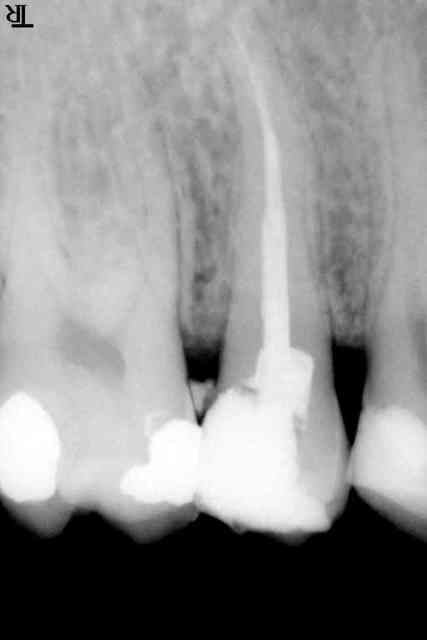

Pour écrire ça, il me faut ravaler ma fierté. Je vous l'assure. Quelle honte !!!! une 15.

Douleur sur une 15 sur laquelle un composite avait été "posé" à peu près 1 an avant.

Douleur spontanée, patati, patata..... Pulpec

J'y vais avec ma para apicale haute, cartouche de chlorhydrate d'articaïne adrénalinée au 1/200000.

Je fais sauter le compo; c'est sensible. Intra ligamentaire c'est encore sensible. Je me dis pulpite chronique ... temporiser. Je dépose complètement le compo. Je curete à minima délicatement et je place dans la cavité un eugénate.

Une semaine après, même protocole et ... même résultat sauf que je finis tant bien que ma le curetage.

Une semaine plus tard, para apicale. Sensible ++.

intraligmantaire. Sensible ++. Intra osseuse (Xtip). Toujours sensible même à l'air ?!?!?

J'ai tout de même mis environ 3 cartouches.

En fait j'ai vu ta radio,et si tu as fait l'anesthesie dans l'axe de la dent,l'apex est à coté, la racine étant coudée,ceci explique peut -être cela!

si tu suis les trajets nerveux, en palatin je vois pas comment (la solution va pas traverser l'os et le grand palatin n'inerve pas là), en paratuberositaire pourquoi pas si linnervation vient de si loin, mais en general apres les racines vest de la 6 bof. peut etre une radio défilée pour essayer de voir ou se situe le bout de la racine par rapport au processus zyg

sinon, superomoyen ou superoanterieur, mais bon tout ça c'est de l'anat, en secteur premo c'est etonnant qu'une paraapicale foire, ou imaginer une recurrence lointaine des filets tres ant du superoant ou un prolongement tres en avant du superopost (paratub)

alors peut être aussi que je l'ai mal faite. Je ne suis pas un expert du Xtip. La radio que j'ai prise avec le foret en place me laisse penser qu'il est orienté trop en distal.